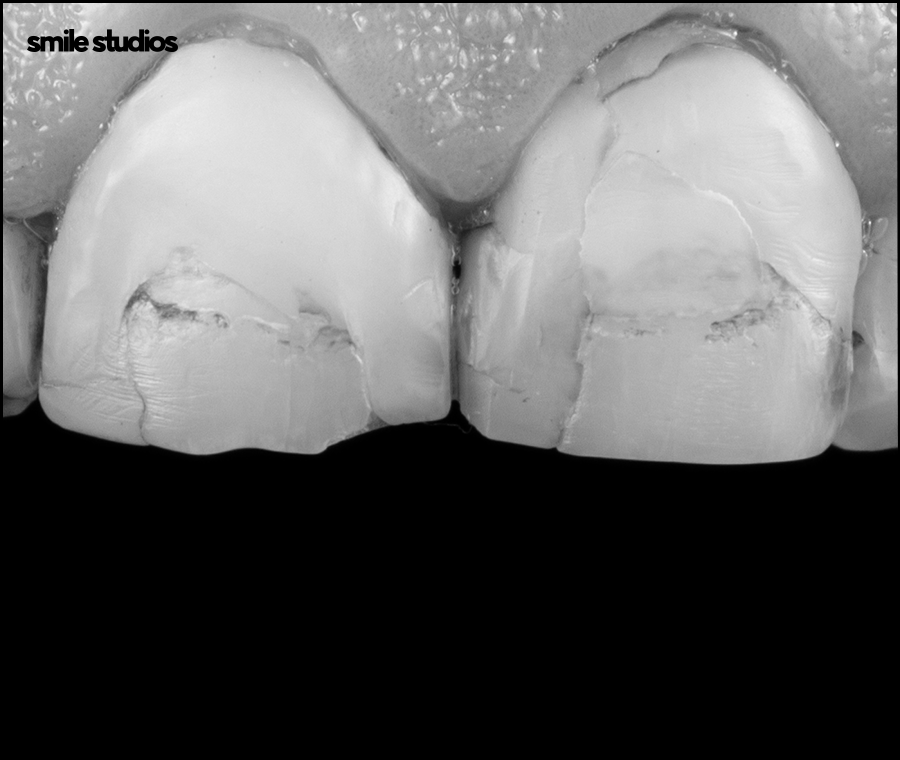

앞니 크랙이 생긴 틈 사이로 이물질이 침투하여 변색될 수 있습니다.

그리고 미세한 틈은 칫솔이 잘 닿지 않아 음식물이 끼기 쉽고 세균이 번식할 환경을 조성하게 됩니다.

아직은 미세한 수준이라고 하더라도 지속적으로 사용하게 되면서 균열이 더 깊어질 수 있는데요.

내부 깊숙한 곳까지 금이 이어지면서 심한 통증을 유발하거나 파절까지 발생하기도 합니다.